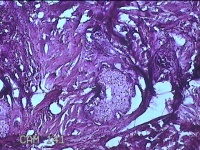

头部肿物

性别

男

年龄

21岁

临床诊断

头皮肿物

一般病史

发现头部结节10余年,无明显疼痛及不适。

标本名称

头部结节

大体所见

灰白暗红色带皮肤样结节1.5x1.3x0.3cm一个,切开结节呈实性,切面灰白粉红色,质软。